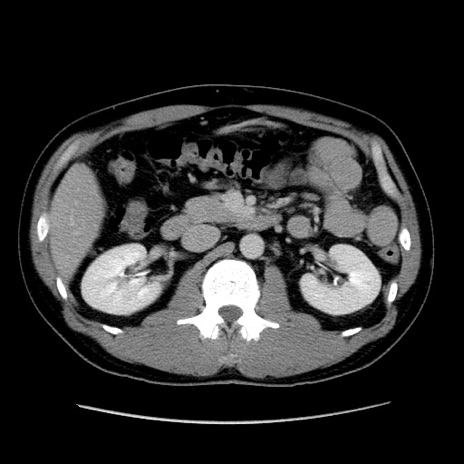

症例4(横断像)

【症例】30歳代男性

【主訴】腹痛、嘔吐

【現病歴】昨晩から突然の腹痛あり、その後嘔吐、軟便も出現。腹痛が改善しないため救急搬送となる。2日前にしめ鯖の食事歴あり。

【身体所見】意識清明、苦悶様、BP 135/90mmHg、BT 35.7℃、腹部:平坦、やや硬、心窩部〜臍部に自発痛、圧痛あり、筋性防御+、反跳痛-

【データ】WBC 8100、CRP 0.57